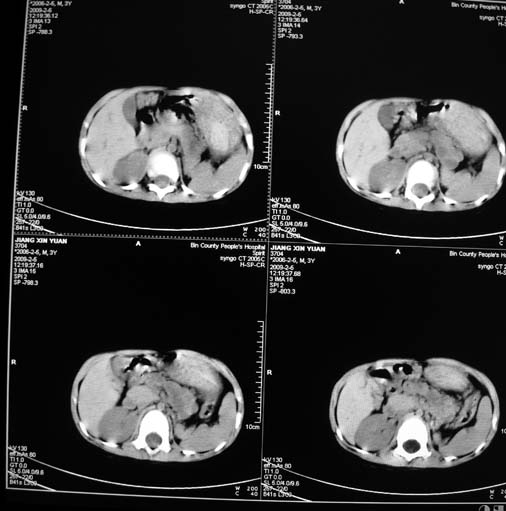

男,3岁,肾母细胞瘤术后,肝脏的低密度是什么?

胰尾下方见两枚囊形灶,肠管?病灶?左侧肾上腺区见团块状影,转移病灶?术后表现?建议与前片对比,肝脏病灶好像有牛眼表现,不除外转移,如果不增强,建议加做个b超,至少可分清其囊性或者实性,又便宜,免费自已给他弄一下也行,对诊断有帮助

左肾母细胞瘤术后,多发性转移可能性大。

左肾母细胞瘤术后:肝脏多发低密度灶,考虑转移可能性大。

左肾母细胞瘤术后:肝脏多发低密度灶,考虑转移可能.请结合临床及增强以及术前检查等